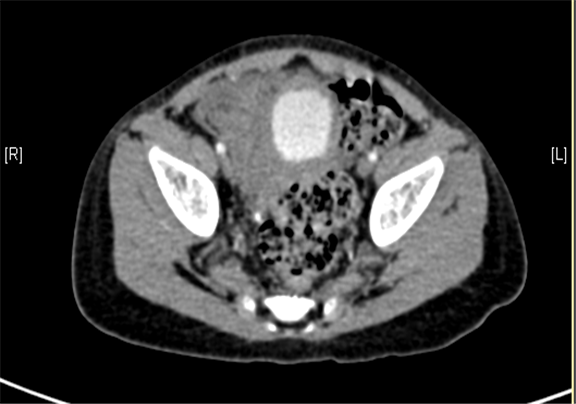

下腹部增强CT示右下腹腔内巨大软组织块影并右肾、输尿管积水。

术前CT检查:

动脉期